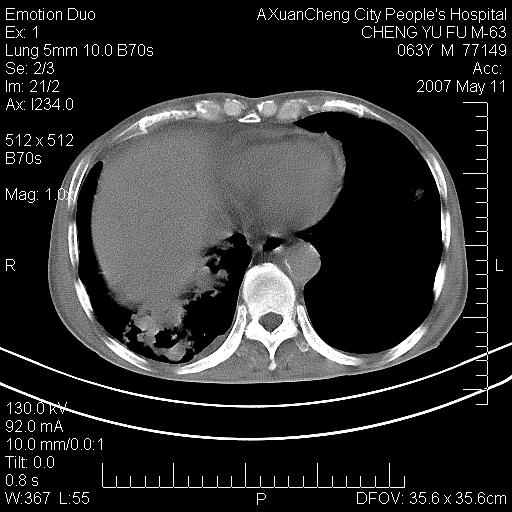

以下是引用小初学者在2007-5-11 19:32:00的发言:[br]1、首先考虑干酪性肺炎支气管播散[br]2、支气管肺泡癌待排

以下是引用zhangzhongshou在2007-5-11 19:30:00的发言:[br]细支气管肺泡癌可能性大。